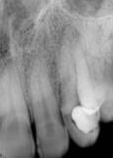

antes depois